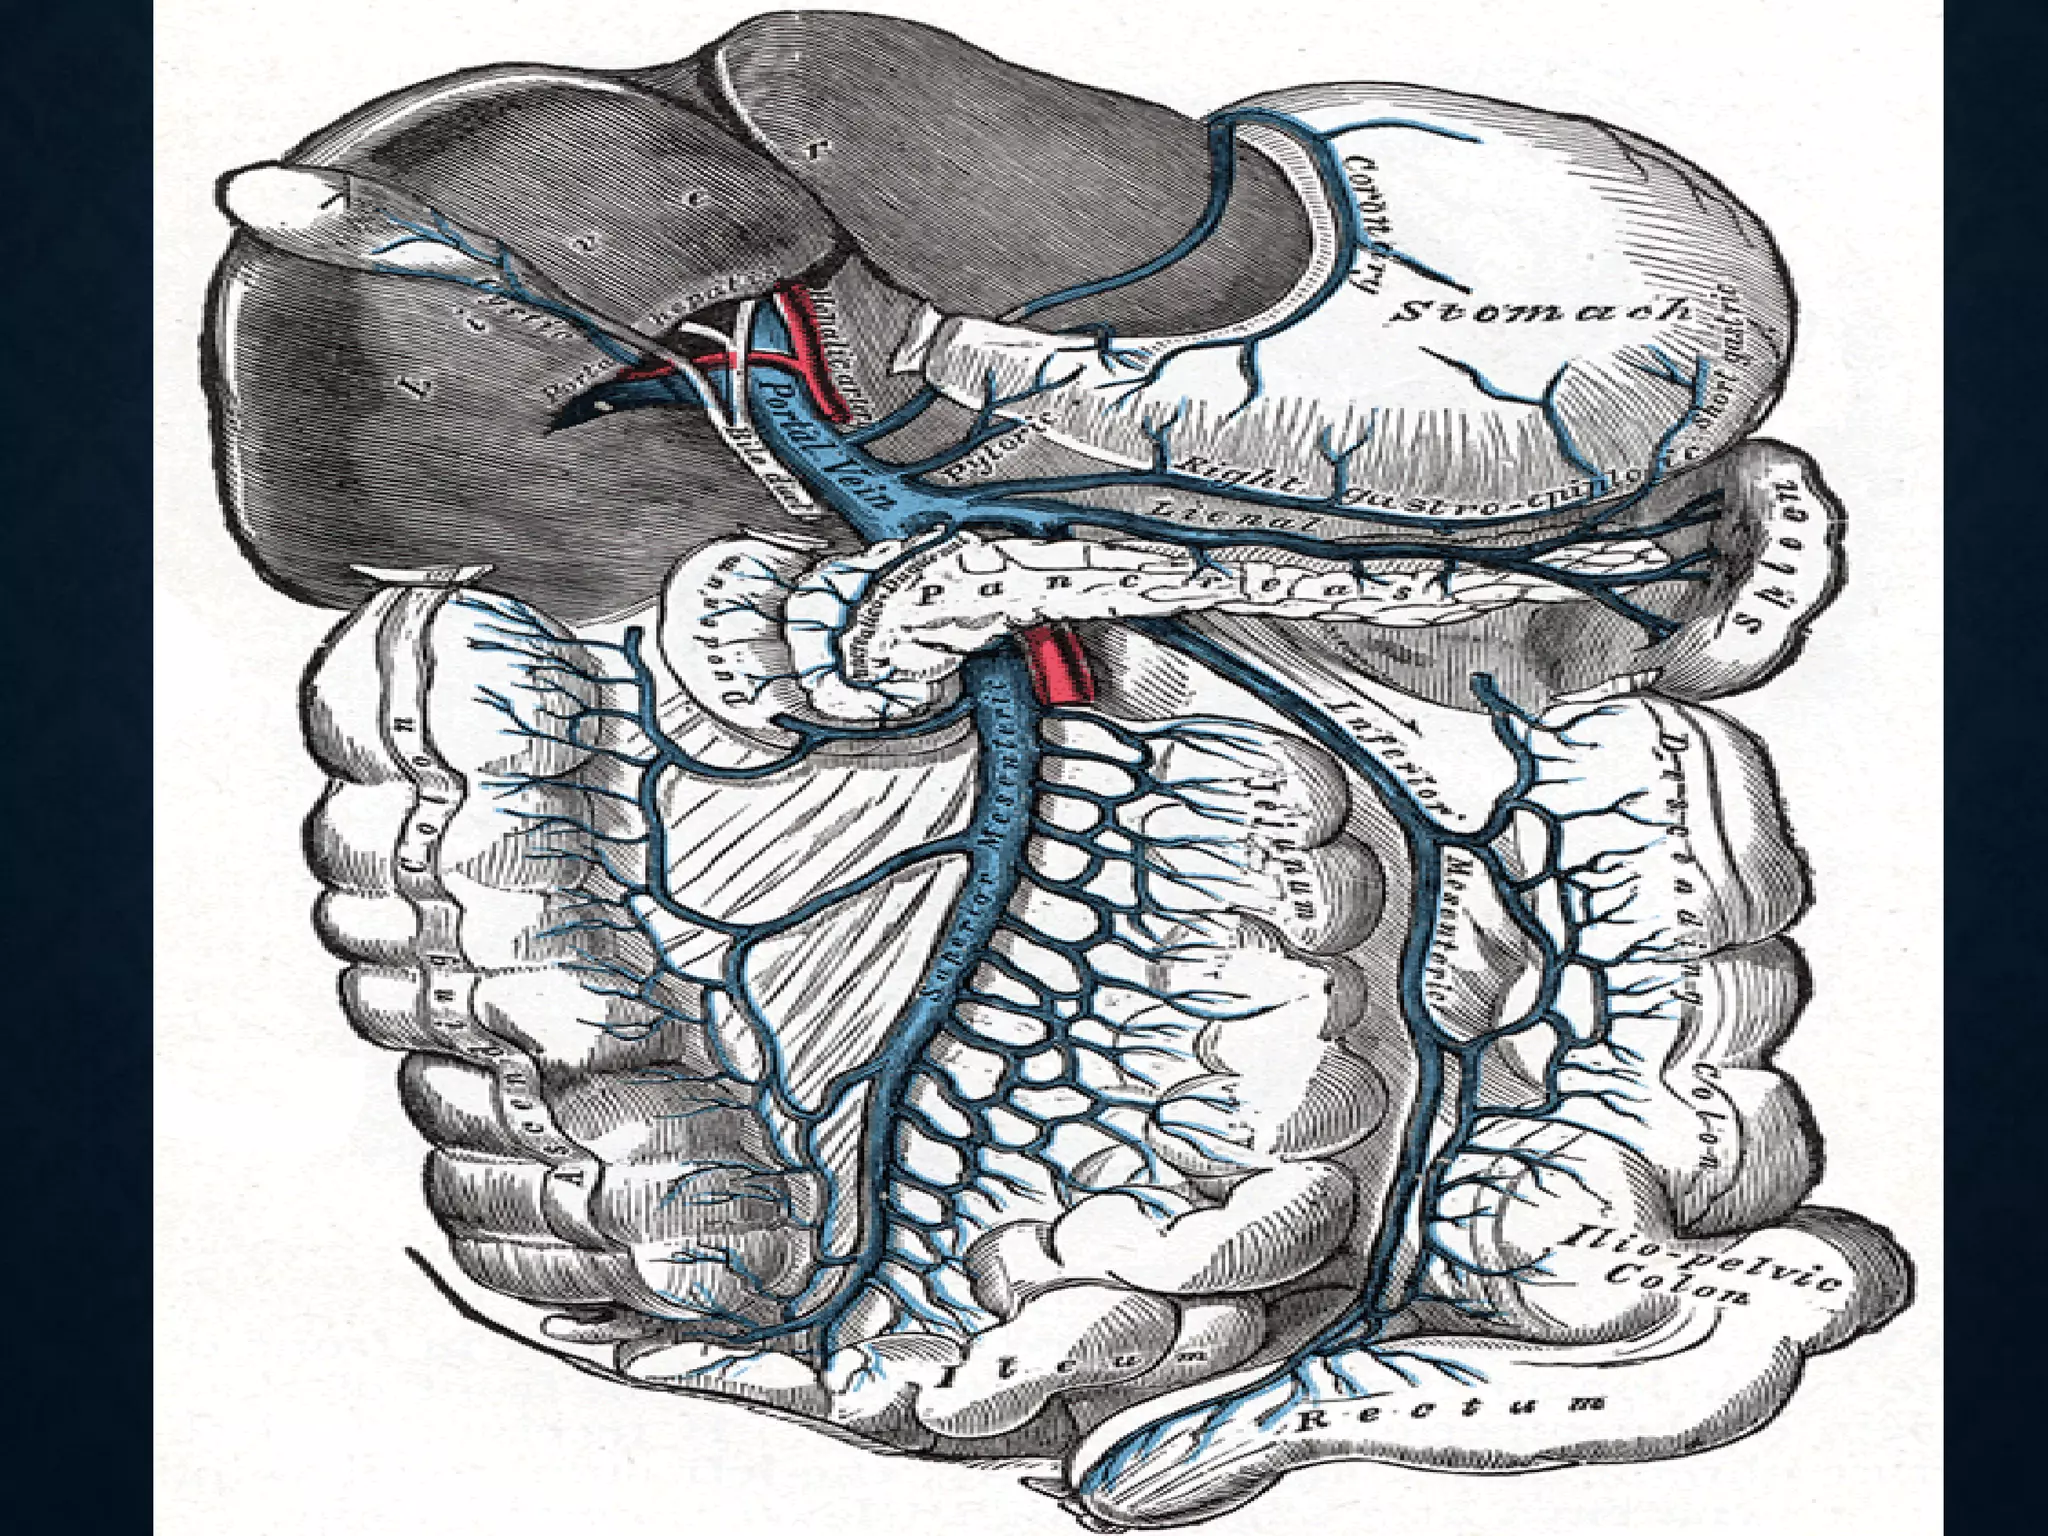

SUPERIOR MESENTERIC VEIN

• In anatomy, the superior mesenteric vein (SMV) is a blood vessel

that drains blood from the small intestine (jejunum and ileum).

• At its termination behind the neck of the pancreas,

• the SMV combines with the splenic vein to form the hepatic portal vein.

• The SMV lies to the right of the similarly named artery, the superior

mesenteric artery, which originates from the abdominal aorta.

SUPERIOR MESENTERIC VEIN •In anatomy, the superior mesenteric vein (SMV) is a blood vessel that drains blood from the small intestine (jejunum and ileum). • At its termination behind the neck of the pancreas, • the SMV combines with the splenic vein to form the hepatic portal vein. • The SMV lies to the right of the similarly named artery, the superior mesenteric artery, which originates from the abdominal aorta.